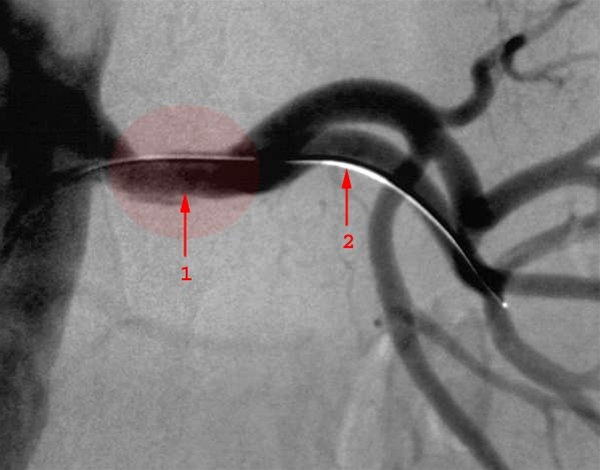

Forsnævring (stenose) (1) i venstre nyrearterie lige efter afgangen fra legemspulsåren (aorta) er behandlet med ballonudvidelse. Ballonen er indført via pulsåren i lysken, ført baglæns op i aorta og så ud i nyrearterien ledt af en guide-wire (2), som er lagt gennem stenosen.